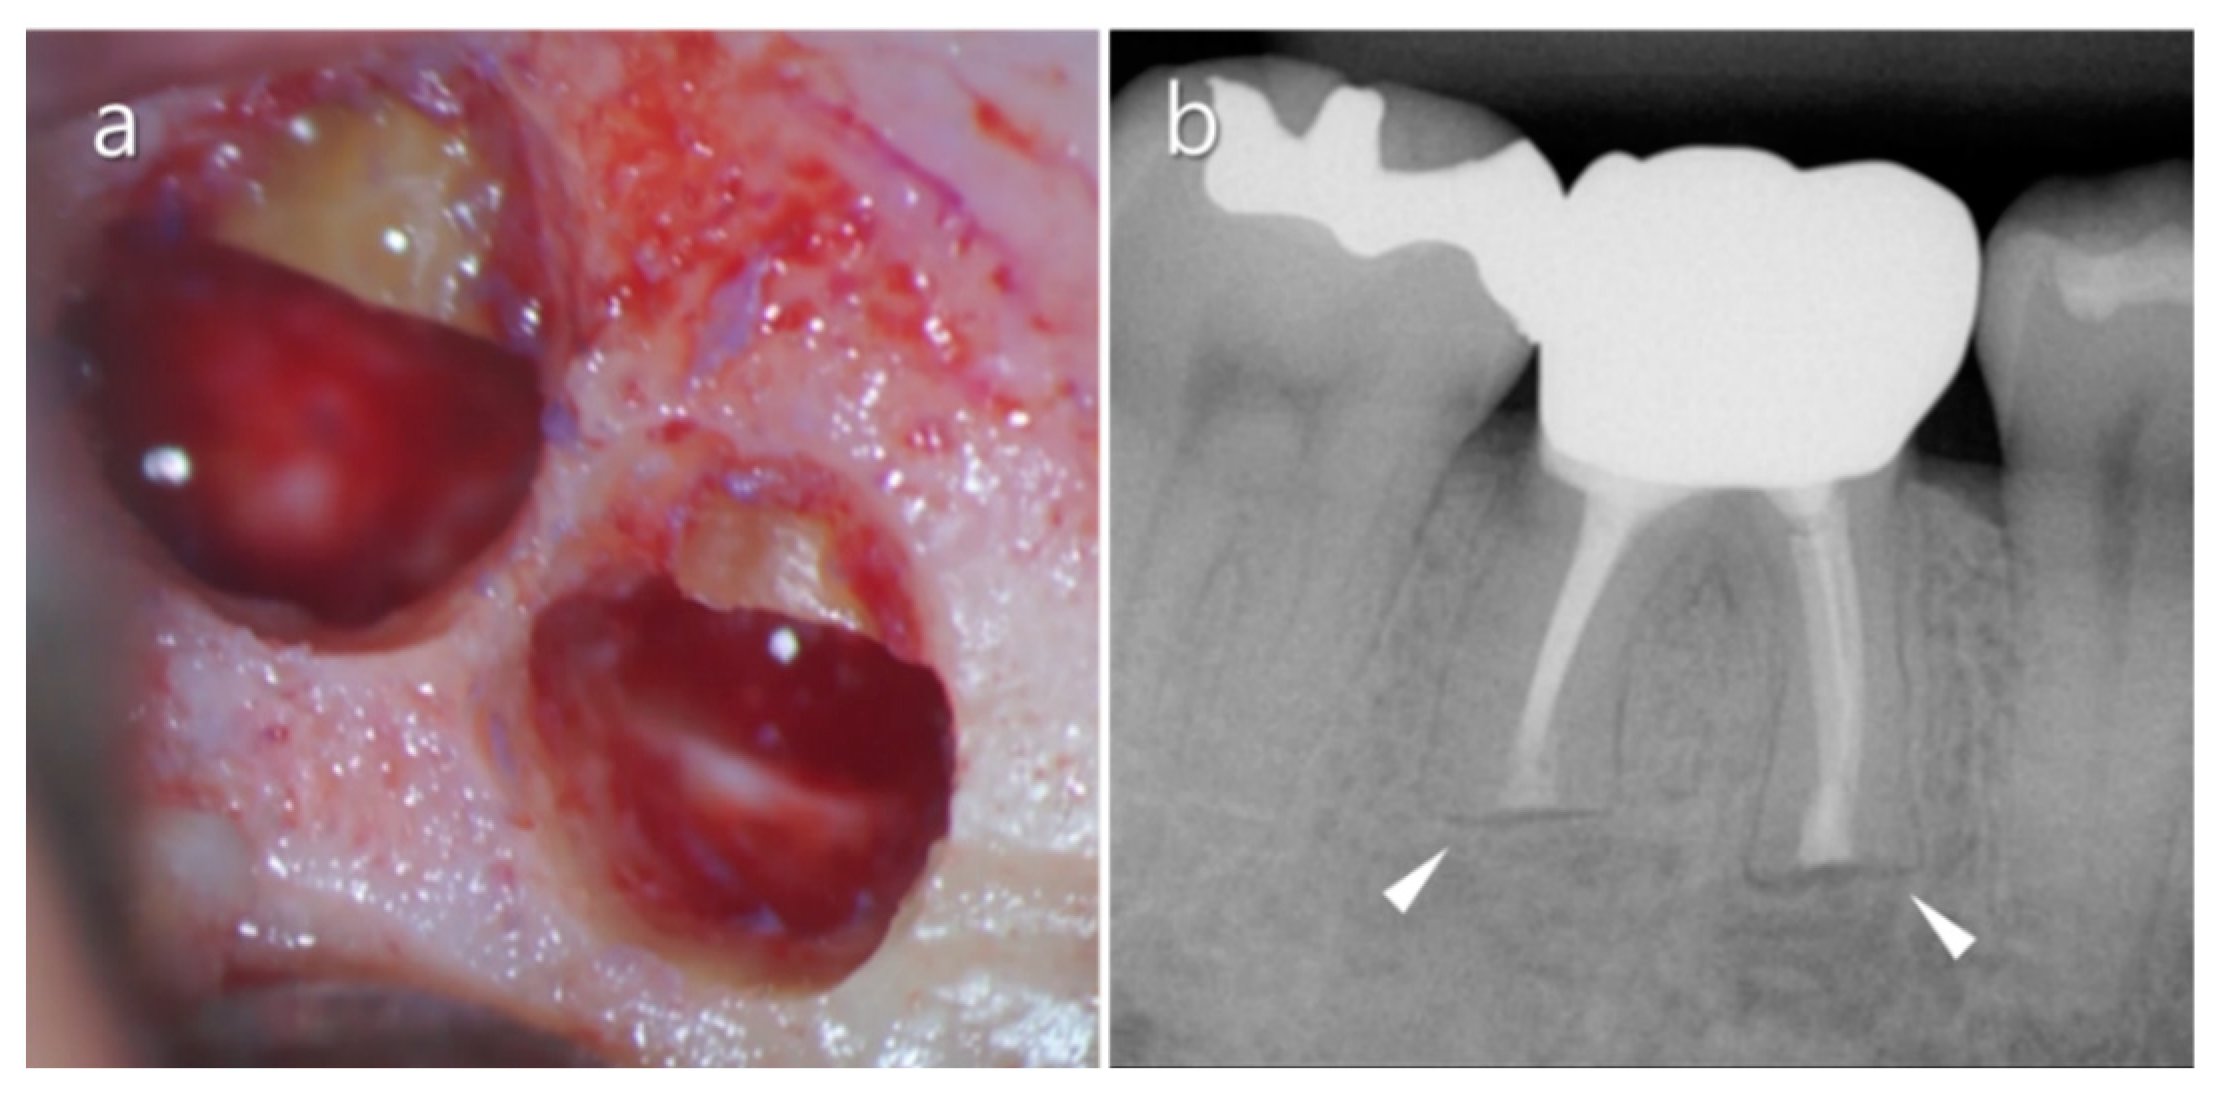

2.3. Mandibular Canal

2.4. Mental Nerve

- Velvart, P.; Hecker, H.; Tillinger, G. Detection of the apical lesion and the mandibular canal in conventional radiography and computed tomography. Oral Surg. Oral Med. Oral Pathol. Oral Radiol. Endod. 2001, 92, 682–688. [Google Scholar] [CrossRef] [PubMed]

- Martí, E.; Peñarrocha, M.; García, B.; Martínez, J.M.; Gay-Escoda, C. Distance between periapical lesion and mandibular canal as a factor in periapical surgery in mandibular molars. J. Oral Maxillofac. Surg. 2008, 66, 2461–2466. [Google Scholar] [CrossRef]